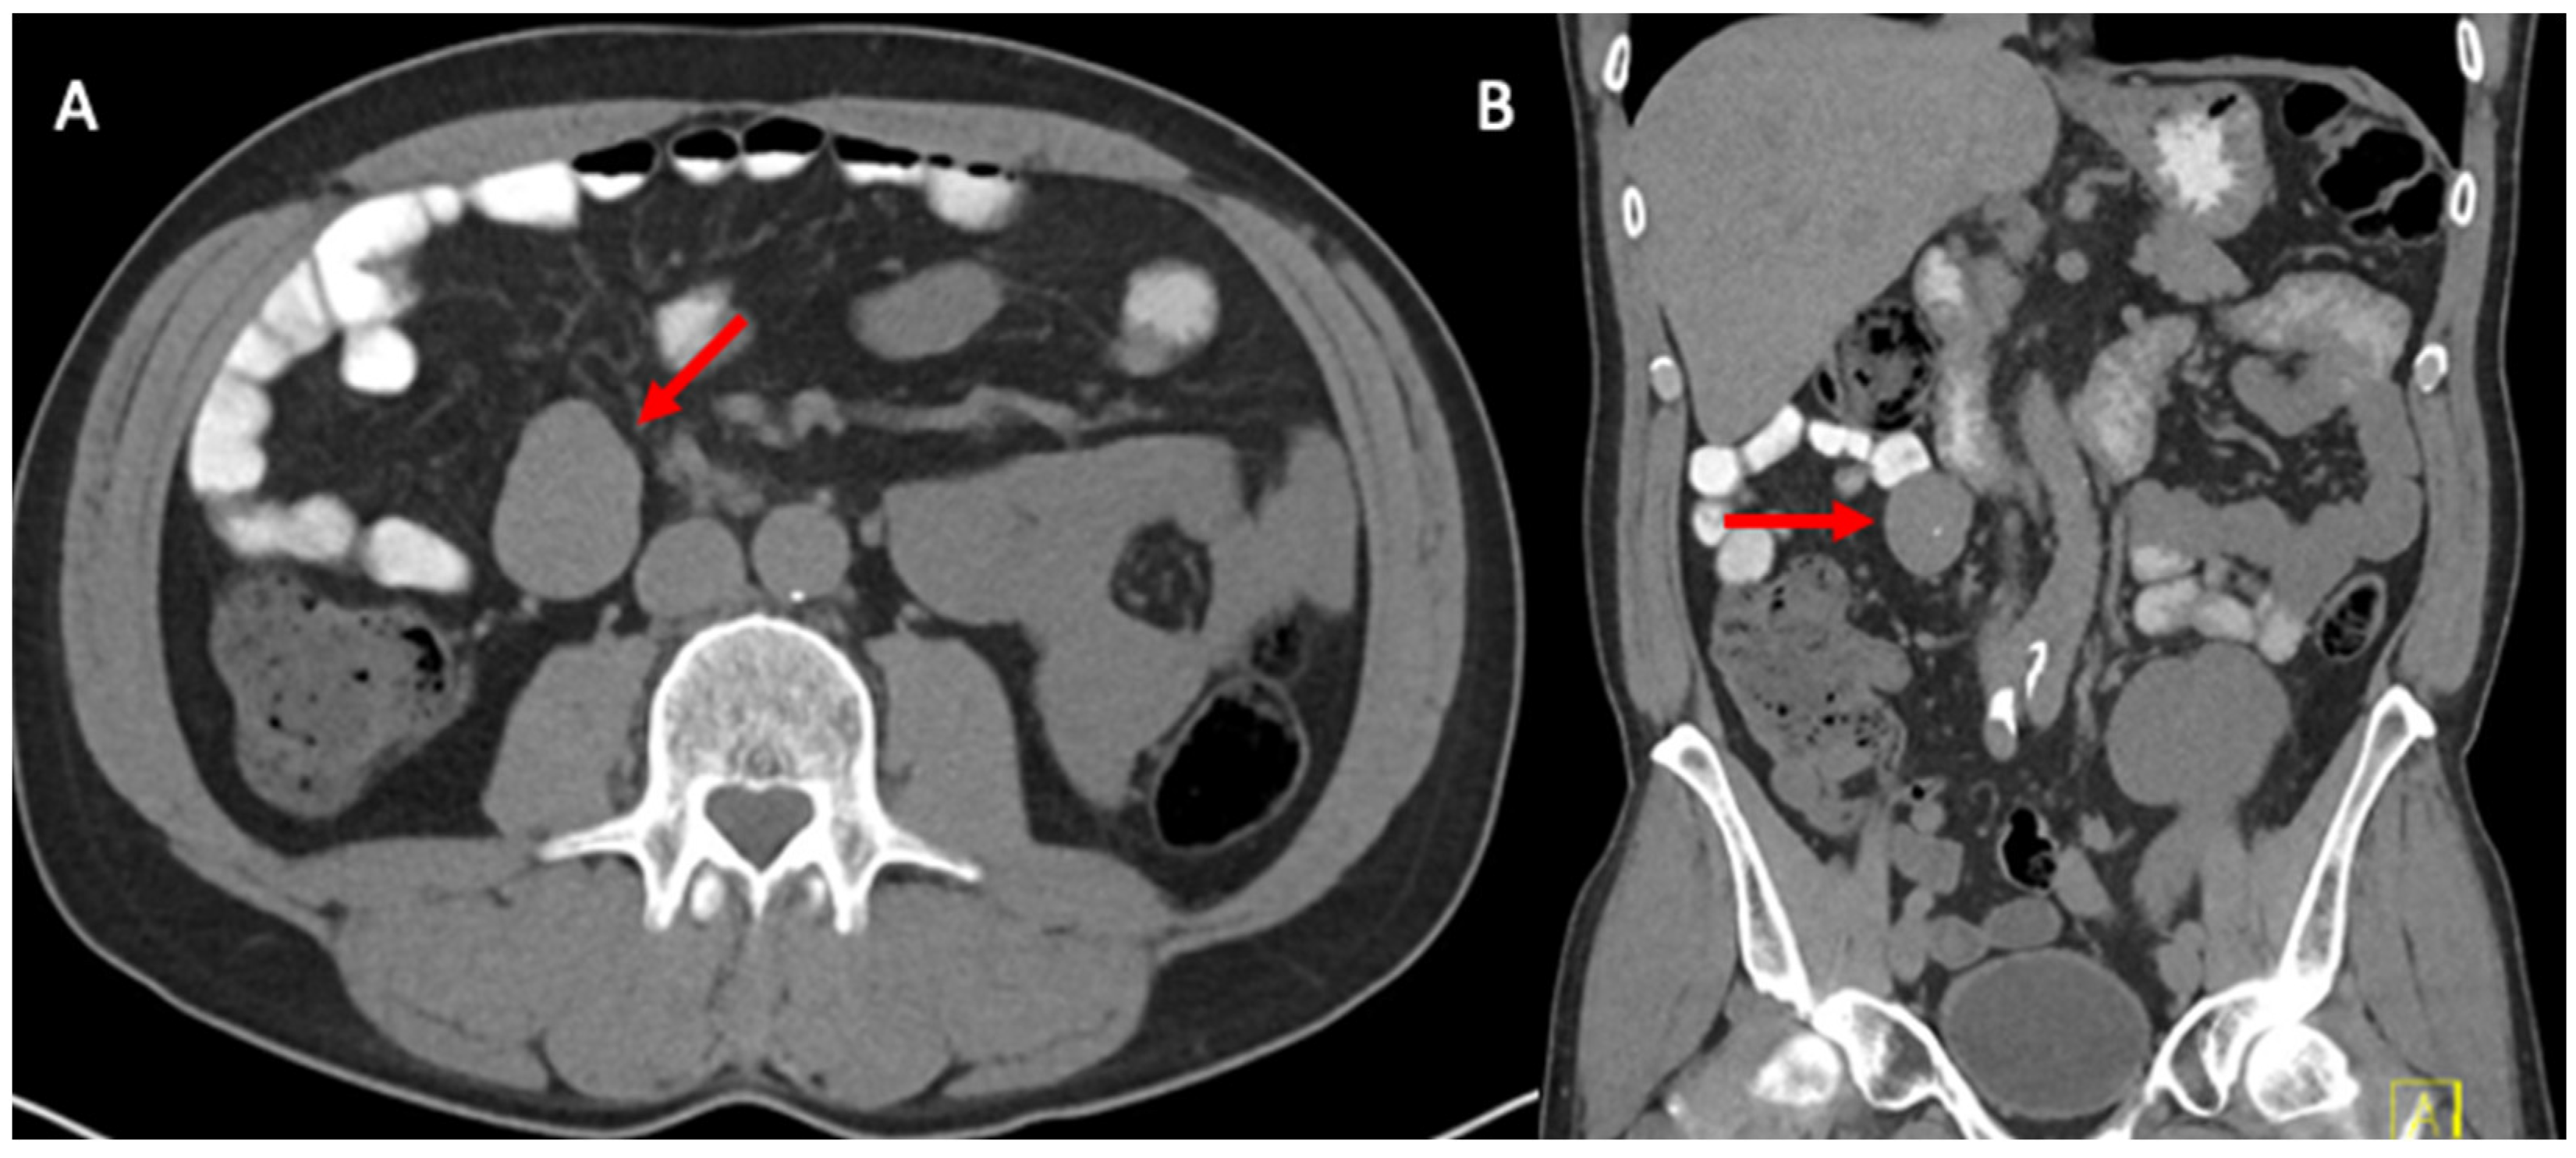

2. Case Report